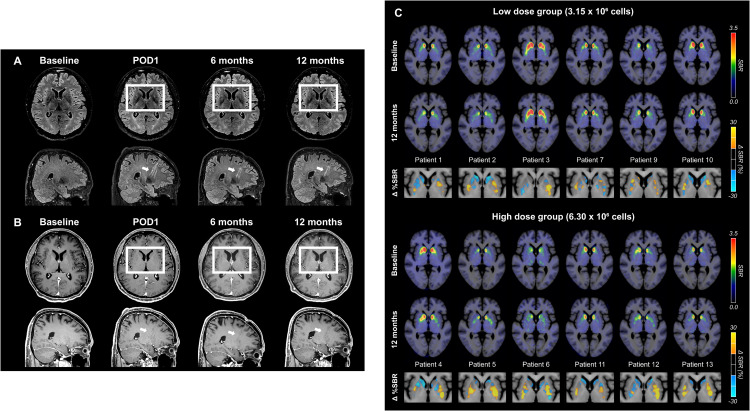

術(shù)后MRI顯示,移植區域未出現腫瘤或明顯炎癥反應,細胞被準確植入殼核目標區域,初步證明手術(shù)和細胞定位的安全性與可控性。

更關(guān)鍵的證據來(lái)自多巴胺轉運體PET成像。與基線(xiàn)相比,后背側殼核區域的DAT信號在高劑量組明顯升高,且這種變化與患者停藥狀態(tài)下的運動(dòng)改善程度呈顯著(zhù)相關(guān)。這意味著(zhù),影像學(xué)上觀(guān)察到的多巴胺能功能增強,與臨床癥狀的改善方向一致。(圖6)

這些結果共同表明:移植的多巴胺祖細胞不僅在腦內存活,而且在關(guān)鍵運動(dòng)環(huán)路中實(shí)現了功能性整合,并與實(shí)際運動(dòng)改善相對應。

圖6:代表性腦部MRI圖像以及A9-DPC移植后18F -FP-CIT攝取量的個(gè)體水平變化